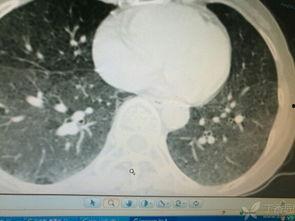

肺玻璃可以帮助医生更准确地诊断肺部疾病,比如肺炎、肺结核、肺癌等。通过观察肺部的透明图像,医生可以清晰地看到病变部位,从而做出更准确的诊断。